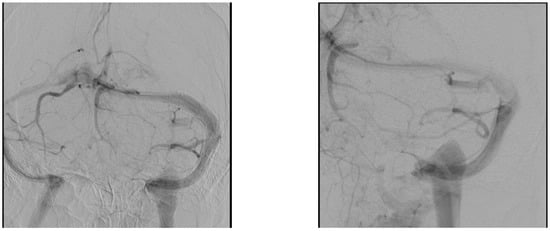

Diagnostic cerebral angiogram with venous manometry was then performed measuring 39 cmH2O in her left transverse sinus and 16 cmH2O in her left sigmoid sinus (Figure A2). The pressure gradient of 23 cmH2O supports the diagnosis of idiopathic intracranial hypertension with left sinus stenosis, and she subsequently underwent left transverse sinus with a post-stenting pressure gradient of 7 cmH2O. After the procedure, her headache improved significantly, and she was able to count her fingers using both eyes. Within 24 h, she also had near complete resolution of her right lateral gaze palsy. She was eventually discharged home on a 6-month course of aspirin and clopidogrel. At 1 month follow-up, the patient continued to show improvement in her visual acuity.

Figure A2. Diagnostic cerebral angiograms—venous phases demonstrating bilateral transverse sinus stenosis.